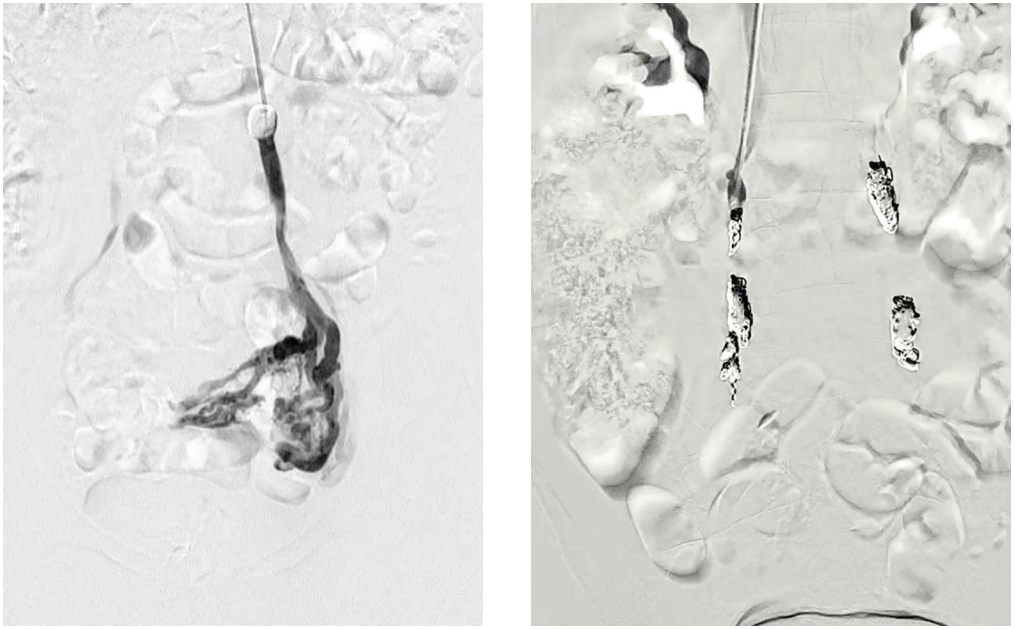

The Ruby, POD, and packing coils are all unique coils for different applications (aneurysm, vessel sacrifice, or space filling) and all designed to be large volume coils to reduce number of implants and cost of the procedure (Figure, Table). We are pushing to use packing coils but are allowing for the use of a POD coil at the top or bottom of the vein for complete safety to prevent any movement. The packing coil, or liquid metal coil, is designed to effectively fill space; the coil is the softest coil Penumbra offers and allows the operator to fill the primary vessel plus the collaterals, achieving complete occlusion of the pelvic veins (see images). The POD is designed with an anchoring distal tip and a proximal portion that becomes smaller/softer for efficient packing. Ruby can be used, but we are not expecting the need for a framing coil, given the POD’s unique ability to anchor within the vessel.

Winokur-Fig2-CLD-MarchApril 2026

Figure 2. Ruby®, POD®, and Packing Coils (Penumbra).

As part of the trial, we are doing injections to look at closure rates. We’re going to pass the coils, inject, and show that it is occlusive.